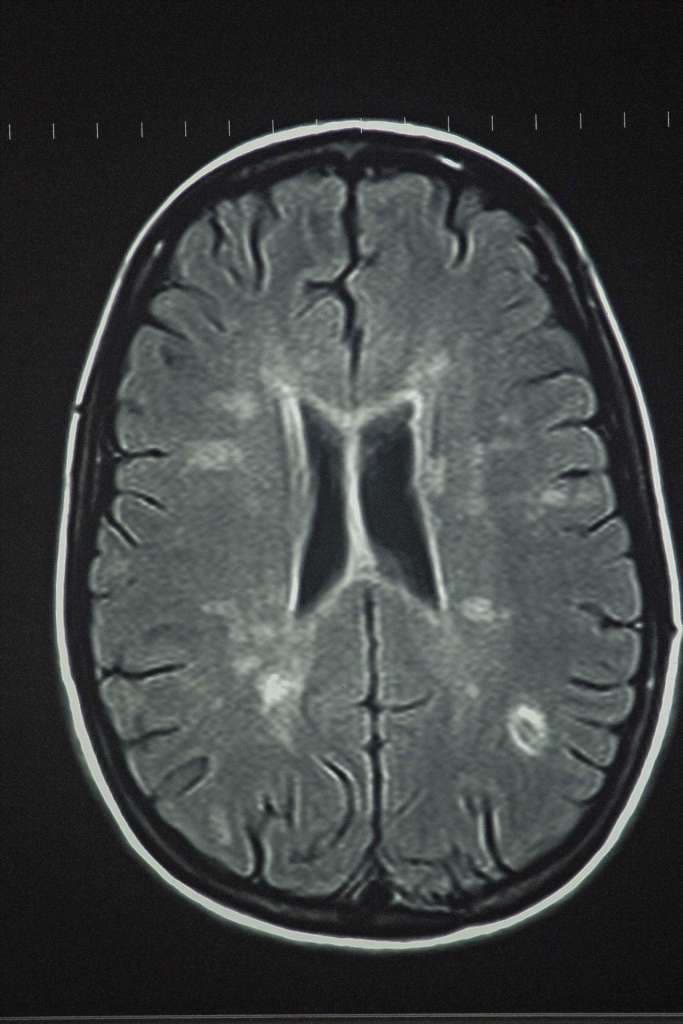

iStock/DeanAustinPhotography